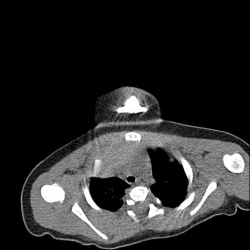

Ж.47 лет, кашель с 3.12.24, темпер-ра до 40 с 23.12.24. Третий курс а/б, без эффекта. Кроме гидроторакса есть значимые изменения в легких?